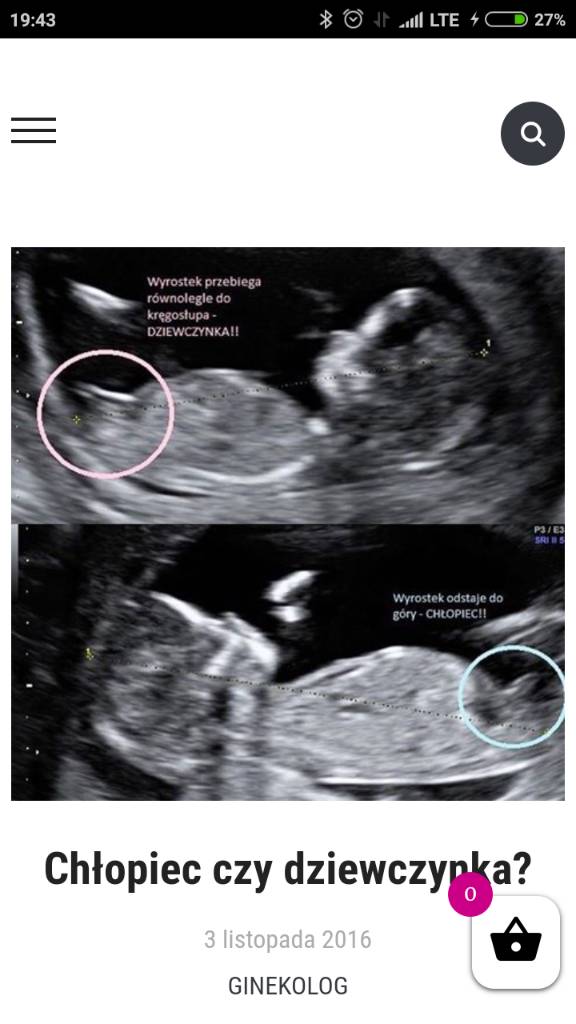

Dziewczynka?Właśnie dziewczyny,które miały już prenatalne [emoji4]znalazłam coś takiego na blogu mamy ginekolog , załączam zdjęcie podgladowe ,oraz zdjęcie swojej dzidzi ..macie podobne zdjęcia w tym ułożeniu ? Jak myślicie co jest u mnie ? :-) Zobacz załącznik 872770Zobacz załącznik 872772